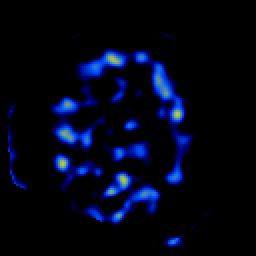

SPECT TL Study #7 -- Slice #45

[Home][Help][Clinical][Tour 1][Tour 2][Tour 3] Slice 45